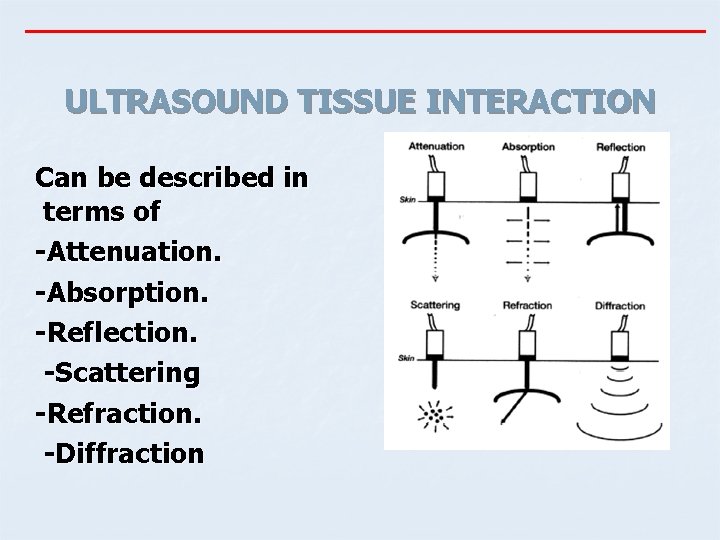

ULTRASOUND TISSUE INTERACTION Can be described in terms of -Attenuation. -Absorption. -Reflection. -Scattering -Refraction. -Diffraction